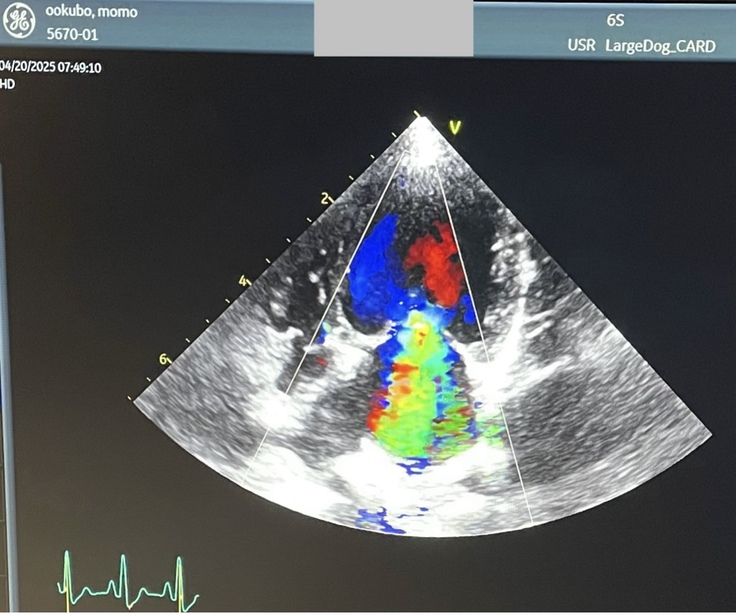

▼閉じていない事による逆流(異常:緑)

下から上に流れるべき血液が逆流しています。(正常:赤・青)